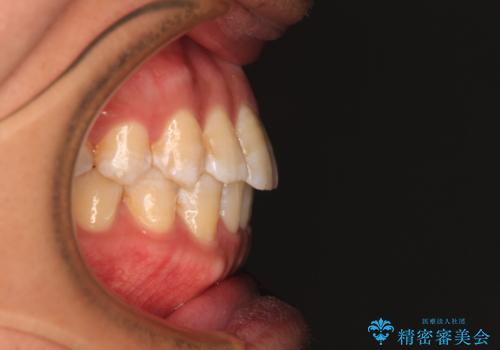

- 前歯のデコボコを気にして来院された患者様です。

インビザラインによるマウスピース矯正も適用となる歯列でしたが、できる限り自己管理の煩わしさのない状態で治したいとのことで、ワイヤー装置にて矯正治療を行うこととしました。